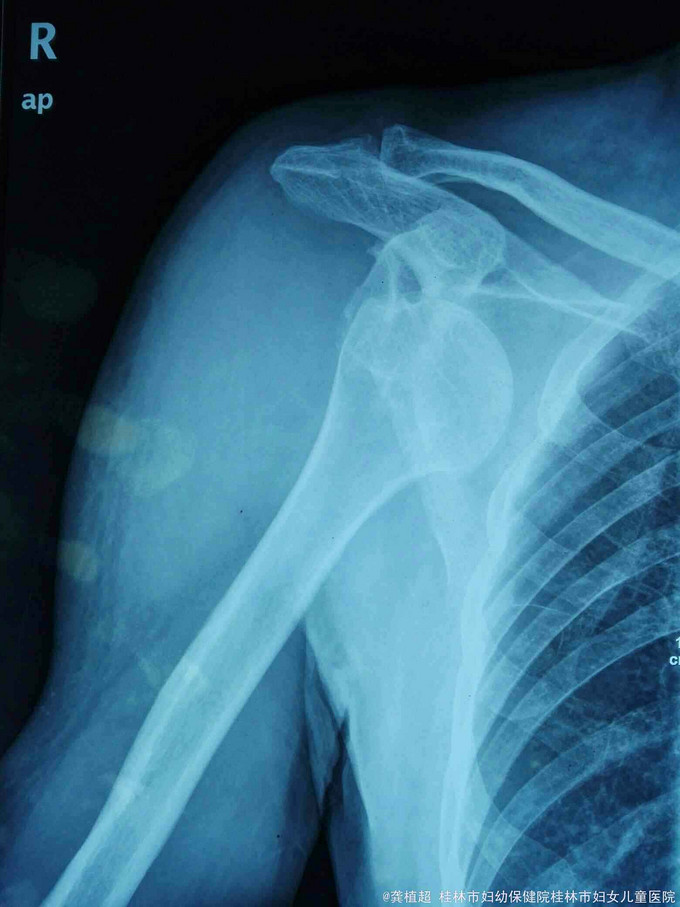

主诉:右肩外伤后疼痛、活动受限27天。 现病史:患者于2015年9月12日不慎跌倒右肩部先着地,右肩部剧烈疼痛、活动受限。肢体无麻木。在家自行外敷草药,症状无缓解。于2015年9月15日到我院门诊行X线检查提示右侧肩关节脱位。门诊予徒手复位术,疼痛明显缓解。术后复查X线示右肩关节复位良好,但患者诉右肩关节仍不能活动,同时伴有右小指麻木,第3、4指伸直受限。近3日上症加重遂来我院,行右上肢肌电图检查提示‘右侧臂丛神经损伤’,予收住院进一步诊治。饮食、睡眠、二便正常。

脊柱无明显畸形,各椎体无明显压、叩痛;右侧上臂近段前侧肿胀明显,右侧肩关节无压痛。右侧肩关节被动活动可,右侧三角肌肌力I级,其余右上肢肌群肌力约Iv级,右侧肩关节不能主动外展及前屈,右侧三角肌区皮肤及右手小指肌小鱼际肌部位浅感觉迟钝。肢端血运良好。

右侧臂丛神经损伤(腋神经、尺神经)

右侧肩关节脱位合并臂丛神经损伤临床少见,目前针对此类疾病的治疗方案如何选择。